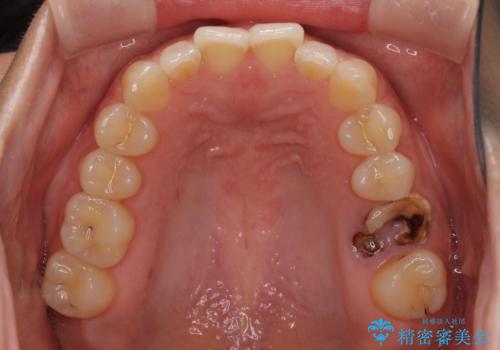

- 抜歯が必要と診断された奥歯を気にして来院された患者様です。

抜歯の上インプラントによる補綴治療を行うこととなりましたが、前歯の叢生も気になるとのことで並行して矯正治療を行うこととしました。

歯列不正は軽微であったので、インビザラインによる矯正治療とし、矯正治療中にインプラント埋入を行う予定としました。

痛みがないので、ボロボロのまま放置していましたが、抜歯後は汚れが溜まりにくくなりスッキリとしたようです。